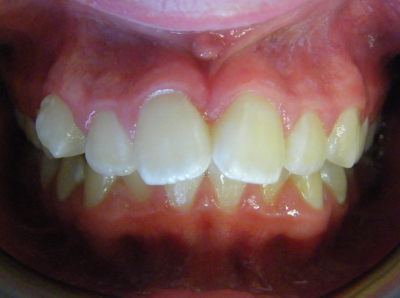

If the top jaw is narrow and there is crowding of the upper teeth or a crossbite (this when the upper teeth bite inside the lower teeth), expansion of the top jaw may be recommended.

An expansion plate widens the top jaw which corrects crossbites and creates space in order to align crowded teeth.

The first two sets of photos below are the before and after photos of a patient who had expansion of the upper jaw followed by upper and lower fixed braces. The third set of photos shows a patient with an expansion plate bonded to the upper teeth and lower fixed braces.